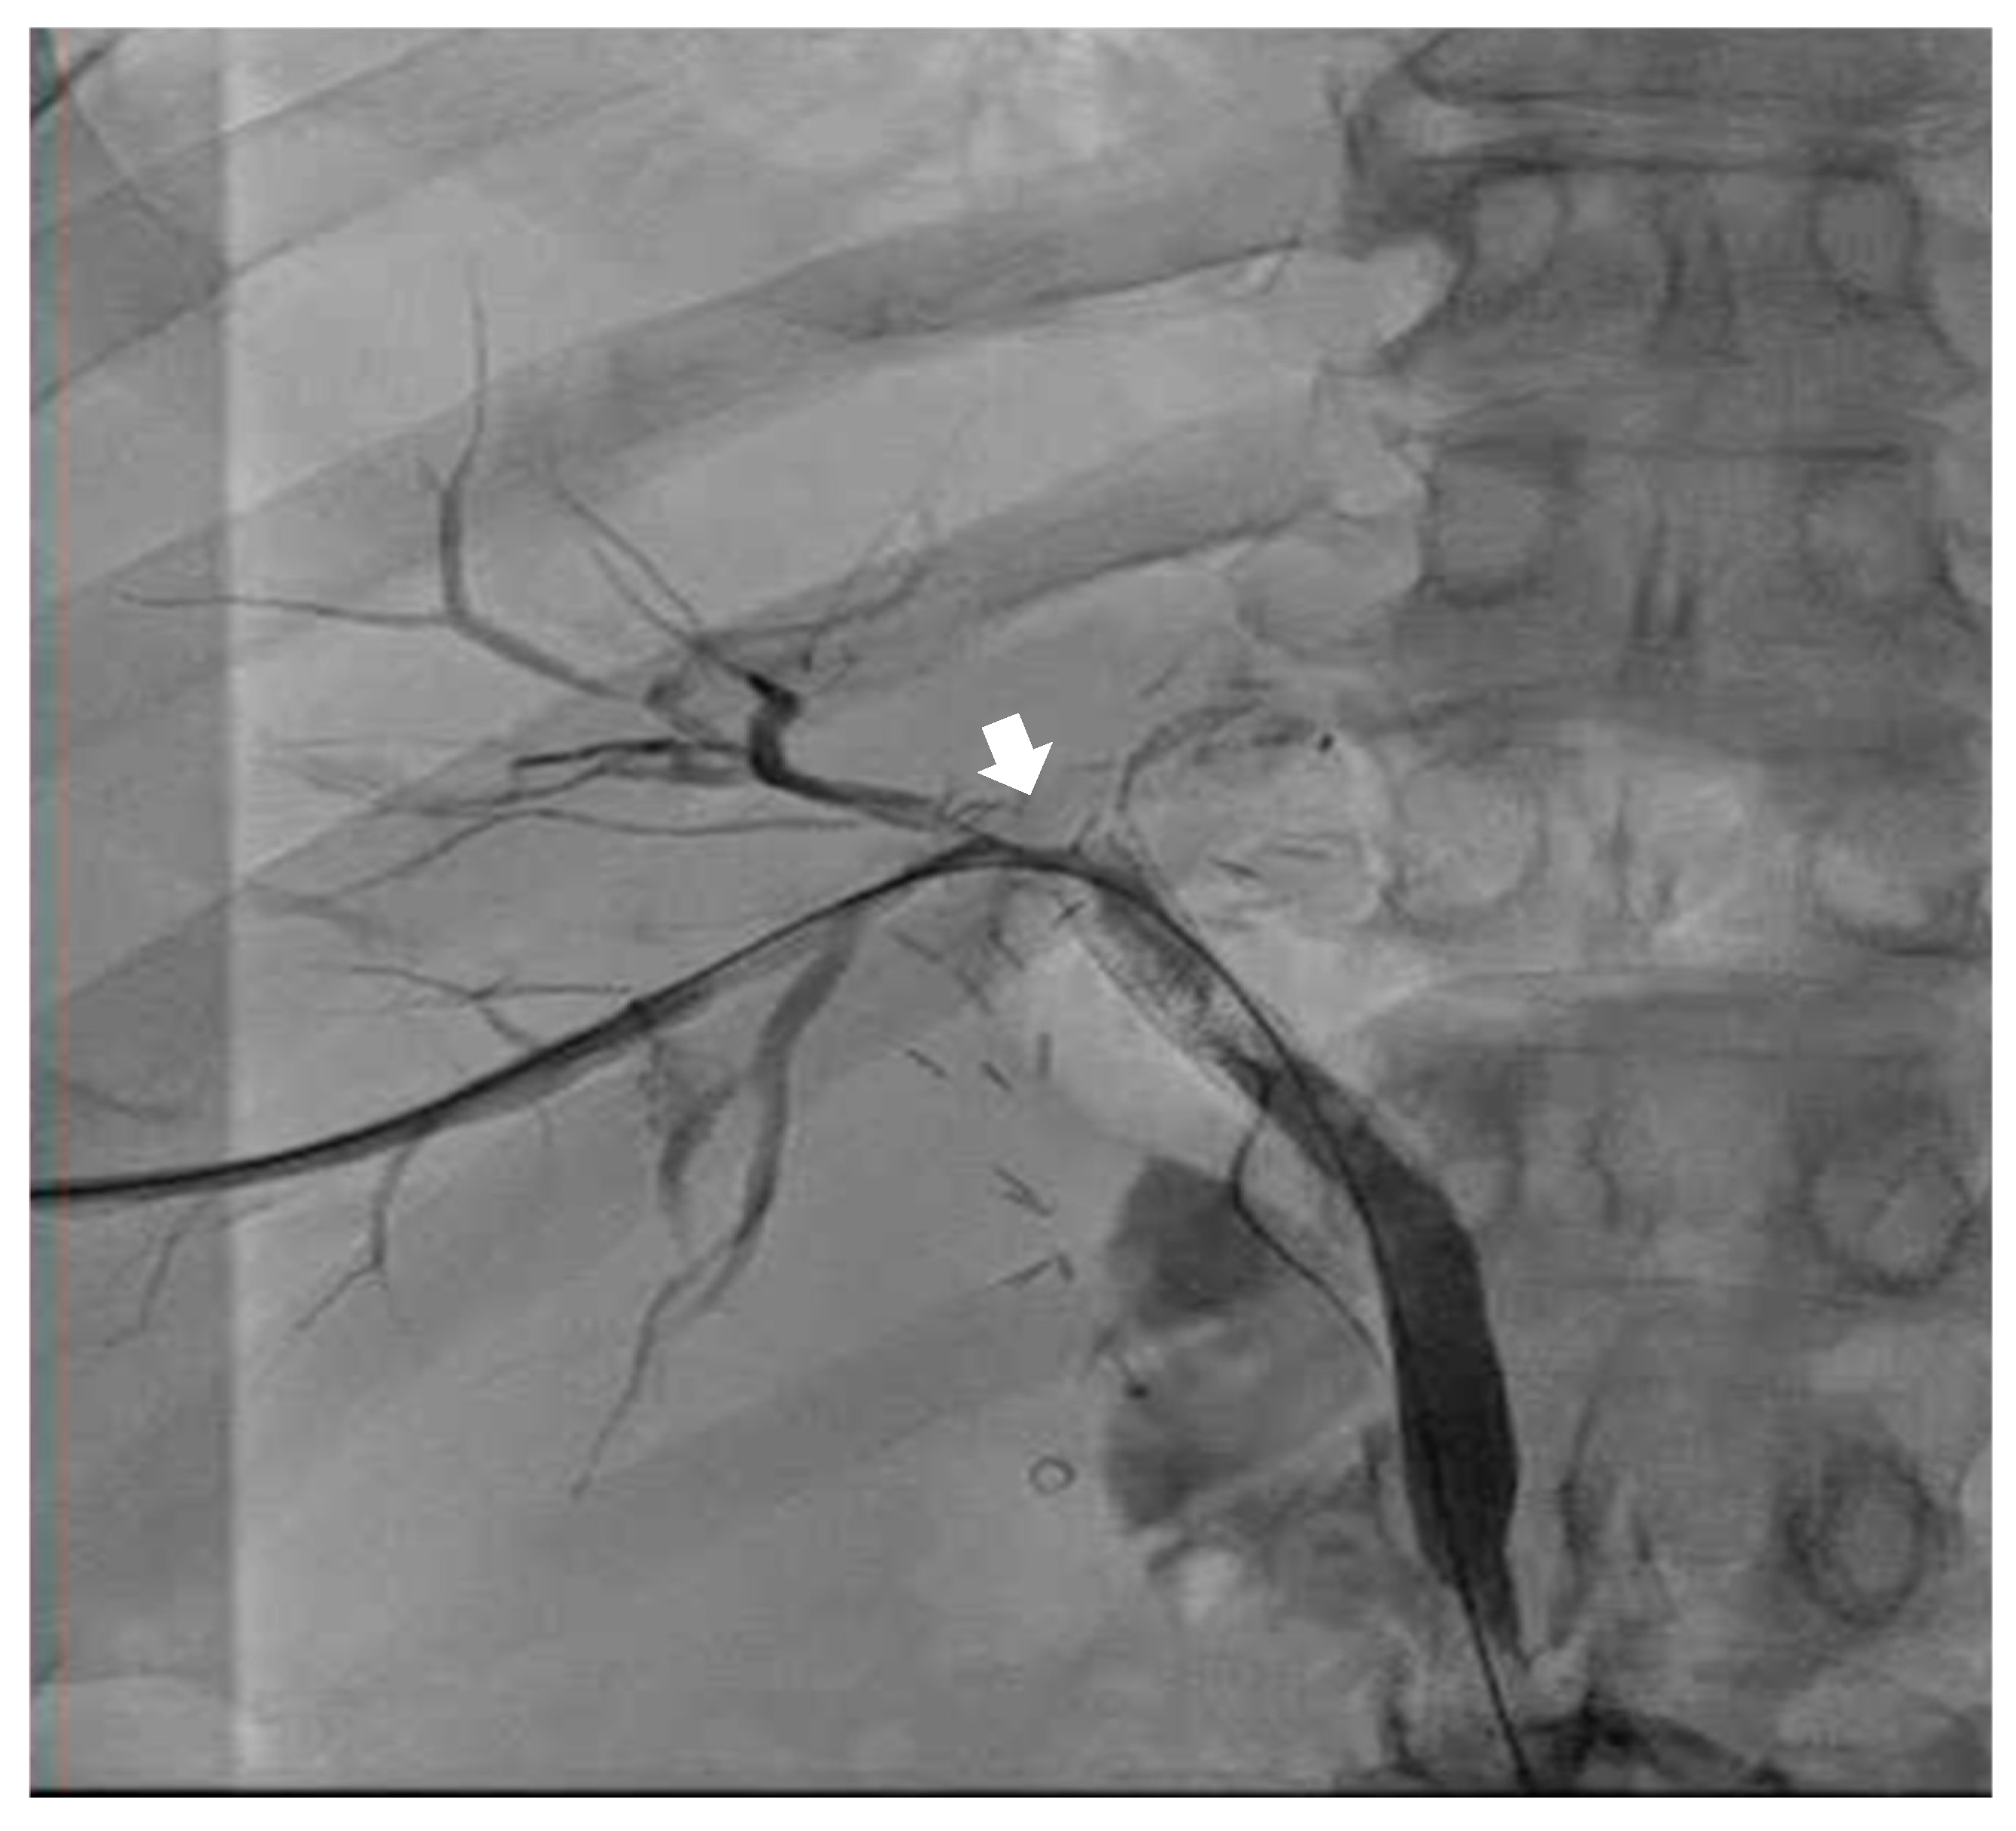

Figure 3. AP interval cholangiogram demonstrating appropriate drainage of the BBF stent. The white arrow demonstrates appropriate drainage through the stent to the external drain.

While in the MICU, the patient was weaned off pressors, and IP conducted another bronchoscopy, which showed thick, bloody secretions in the right lower lobe airway. There were no obvious secretions in the left airway. Therapeutic suctioning was performed. The patient remained intubated during post-operative day one and was started on a five-day course of Zosyn given the acute infiltrations seen on chest X-ray in the right lung (see Figure 2). Bile cultures were negative. The patient was extubated on post-operative day two with the difficult airway team present. The patient was alert and oriented to person, place, and time with appropriate biliary drain function (200 cc/day) and ambulating with assistance (ICU mobility level 8). In April 2024, the patient underwent a staging cholangiogram with internalization of the biliary drain (see Figure 3). Finally, the patient underwent a successful embolization of the biliary-pleural fistula in March 2024.